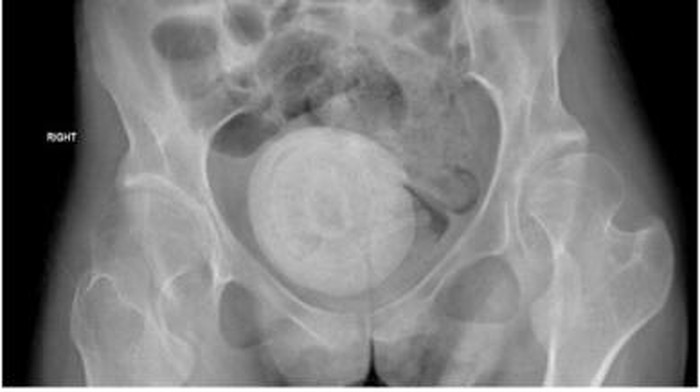

Ia kemudian menjalani pemeriksaan ginekologi dan dokter memastikan ada 'batu' seukuran jeruk besar di antara organ panggulnya.

Setelah dipecah menjadi beberapa bagian, batu-batu tersebut dikeluarkan menggunakan tang saat operasi yang berlangsung selama tiga jam. Batu vagina yang bersarang di antara organ panggul wanita tersebut sangat besar sehingga menekan kandung kemihnya. Kondisi ini mengurangi kapasitas dan menyebabkan kebocoran urine.